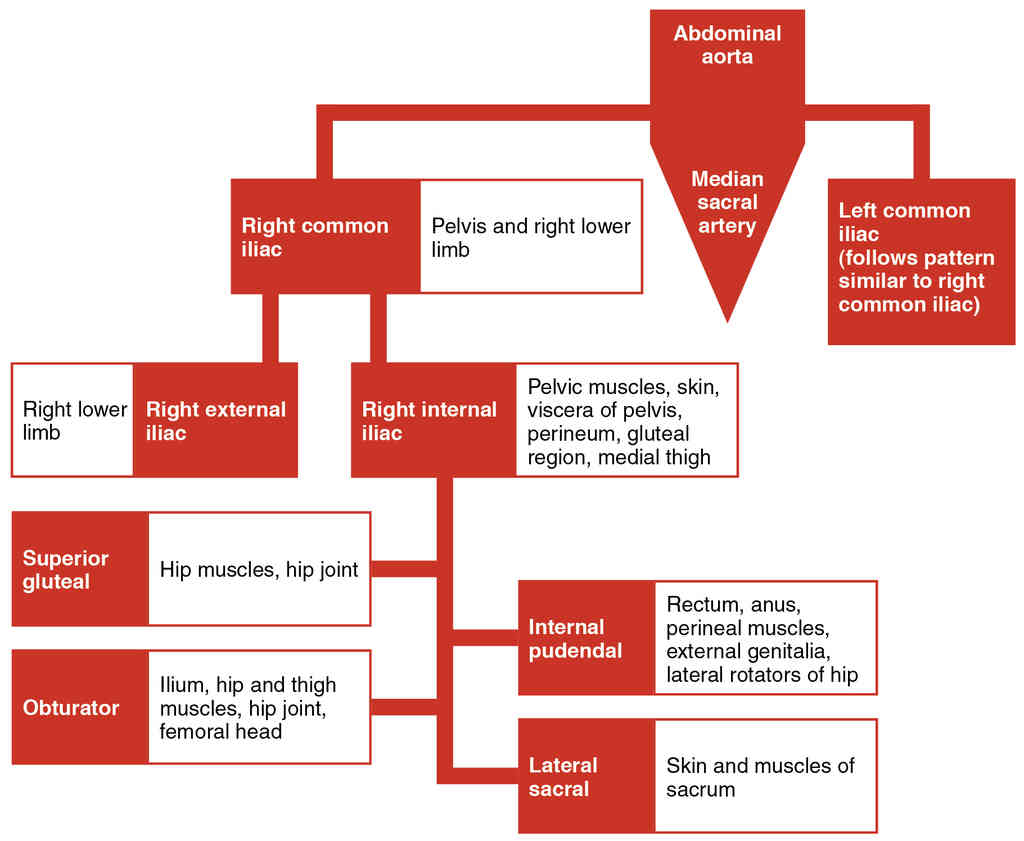

This page is under construction. For now, it is just a resource of the images found in the OpenStax Anatomy and Physiology Handbook. It wil slowly change into a revision tool. Each slide has a number. Use this to refer to the slide. When completed, it will have an unlabelled section, with labelled slides in parallel. On the unlabelled slides, write your answer and use the labelled slide to assess yourself. Keep track by also noting the number on each slide. Improvement at each attempt is important, more so than full marks on a first attempt.